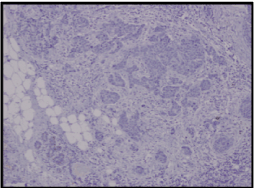

A wide local excision of the tumour was done (Figure3), which was reported as a 5x2x1.5cm irregular mass composed of cells arranged in fused glandular formation and cribriform pattern, consistent with metastatic adenocarcinoma (Slide 4). The tumour cells are positive for ER (Slide 5), PR (Slide 6), CK7, E-cadherin and mammaglobin. The immunoprofile is consistent with a metastatic breast carcinoma. The underlying skeletal muscle was uninvolved.

Slide 5. Section from metastatic tumour shows Estrogen Receptor positivity.

Slide 6. Section from metastatic tumour shows Progesterone Receptor positivity.

The other interesting thing noted was the change in immunochemistry of the metastatic lesion. The primary tumour was estrogen and progesterone negative, and Her-2 positive. The metastatic nodule however was noted to be estrogen and progesterone positive. Niikura et al had reported that the incidence of discordance for ER, PR and HER2 between primary and metastatic tumours was 18.4%, 40.3% and 13.6% respectively [5]. As there are no clear treatment guidelines for such metastatic lesions, this change in immunohistochemistry provided us the option of putting the patient on hormonal therapy in the hope that it would control the disease. Treatment has to be individualized, based on the prognosis of the patient [6].